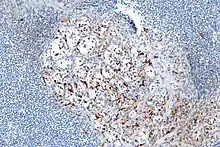

- About 40% of carcinoids have a scattering of sustentacular cells, which stain positive for S-100.[6]

Micrograph highlighting the sustentacular cells in a paraganglioma. S100 immunostain